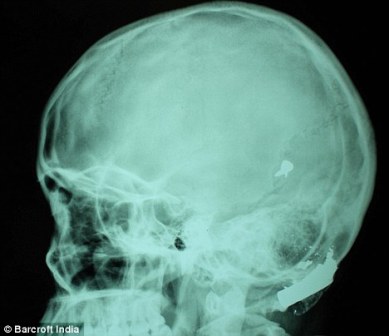

其中一顆子彈擊中她的左中耳,穿透了她的耳骨,然后擊中頭骨,嵌在了腦子里。另外兩顆子彈分別擊中她的右臂和心臟。印度Lok Nayak醫(yī)院的醫(yī)生稱,赫娜能夠康復(fù)完全是奇跡,她也足夠幸運(yùn)。她的主治醫(yī)生稱:“當(dāng)我們看到她的情況時(shí),被嚇了一跳,幸運(yùn)的是她活了下來。”

這顆子彈沒有損壞大腦中控制身體機(jī)能的部分。盡管赫娜的手術(shù)很成功,但醫(yī)生表示,她還有出現(xiàn)感染和并發(fā)癥的可能。子彈毀掉了她的中耳,可能導(dǎo)致她耳聾。(楊柳)